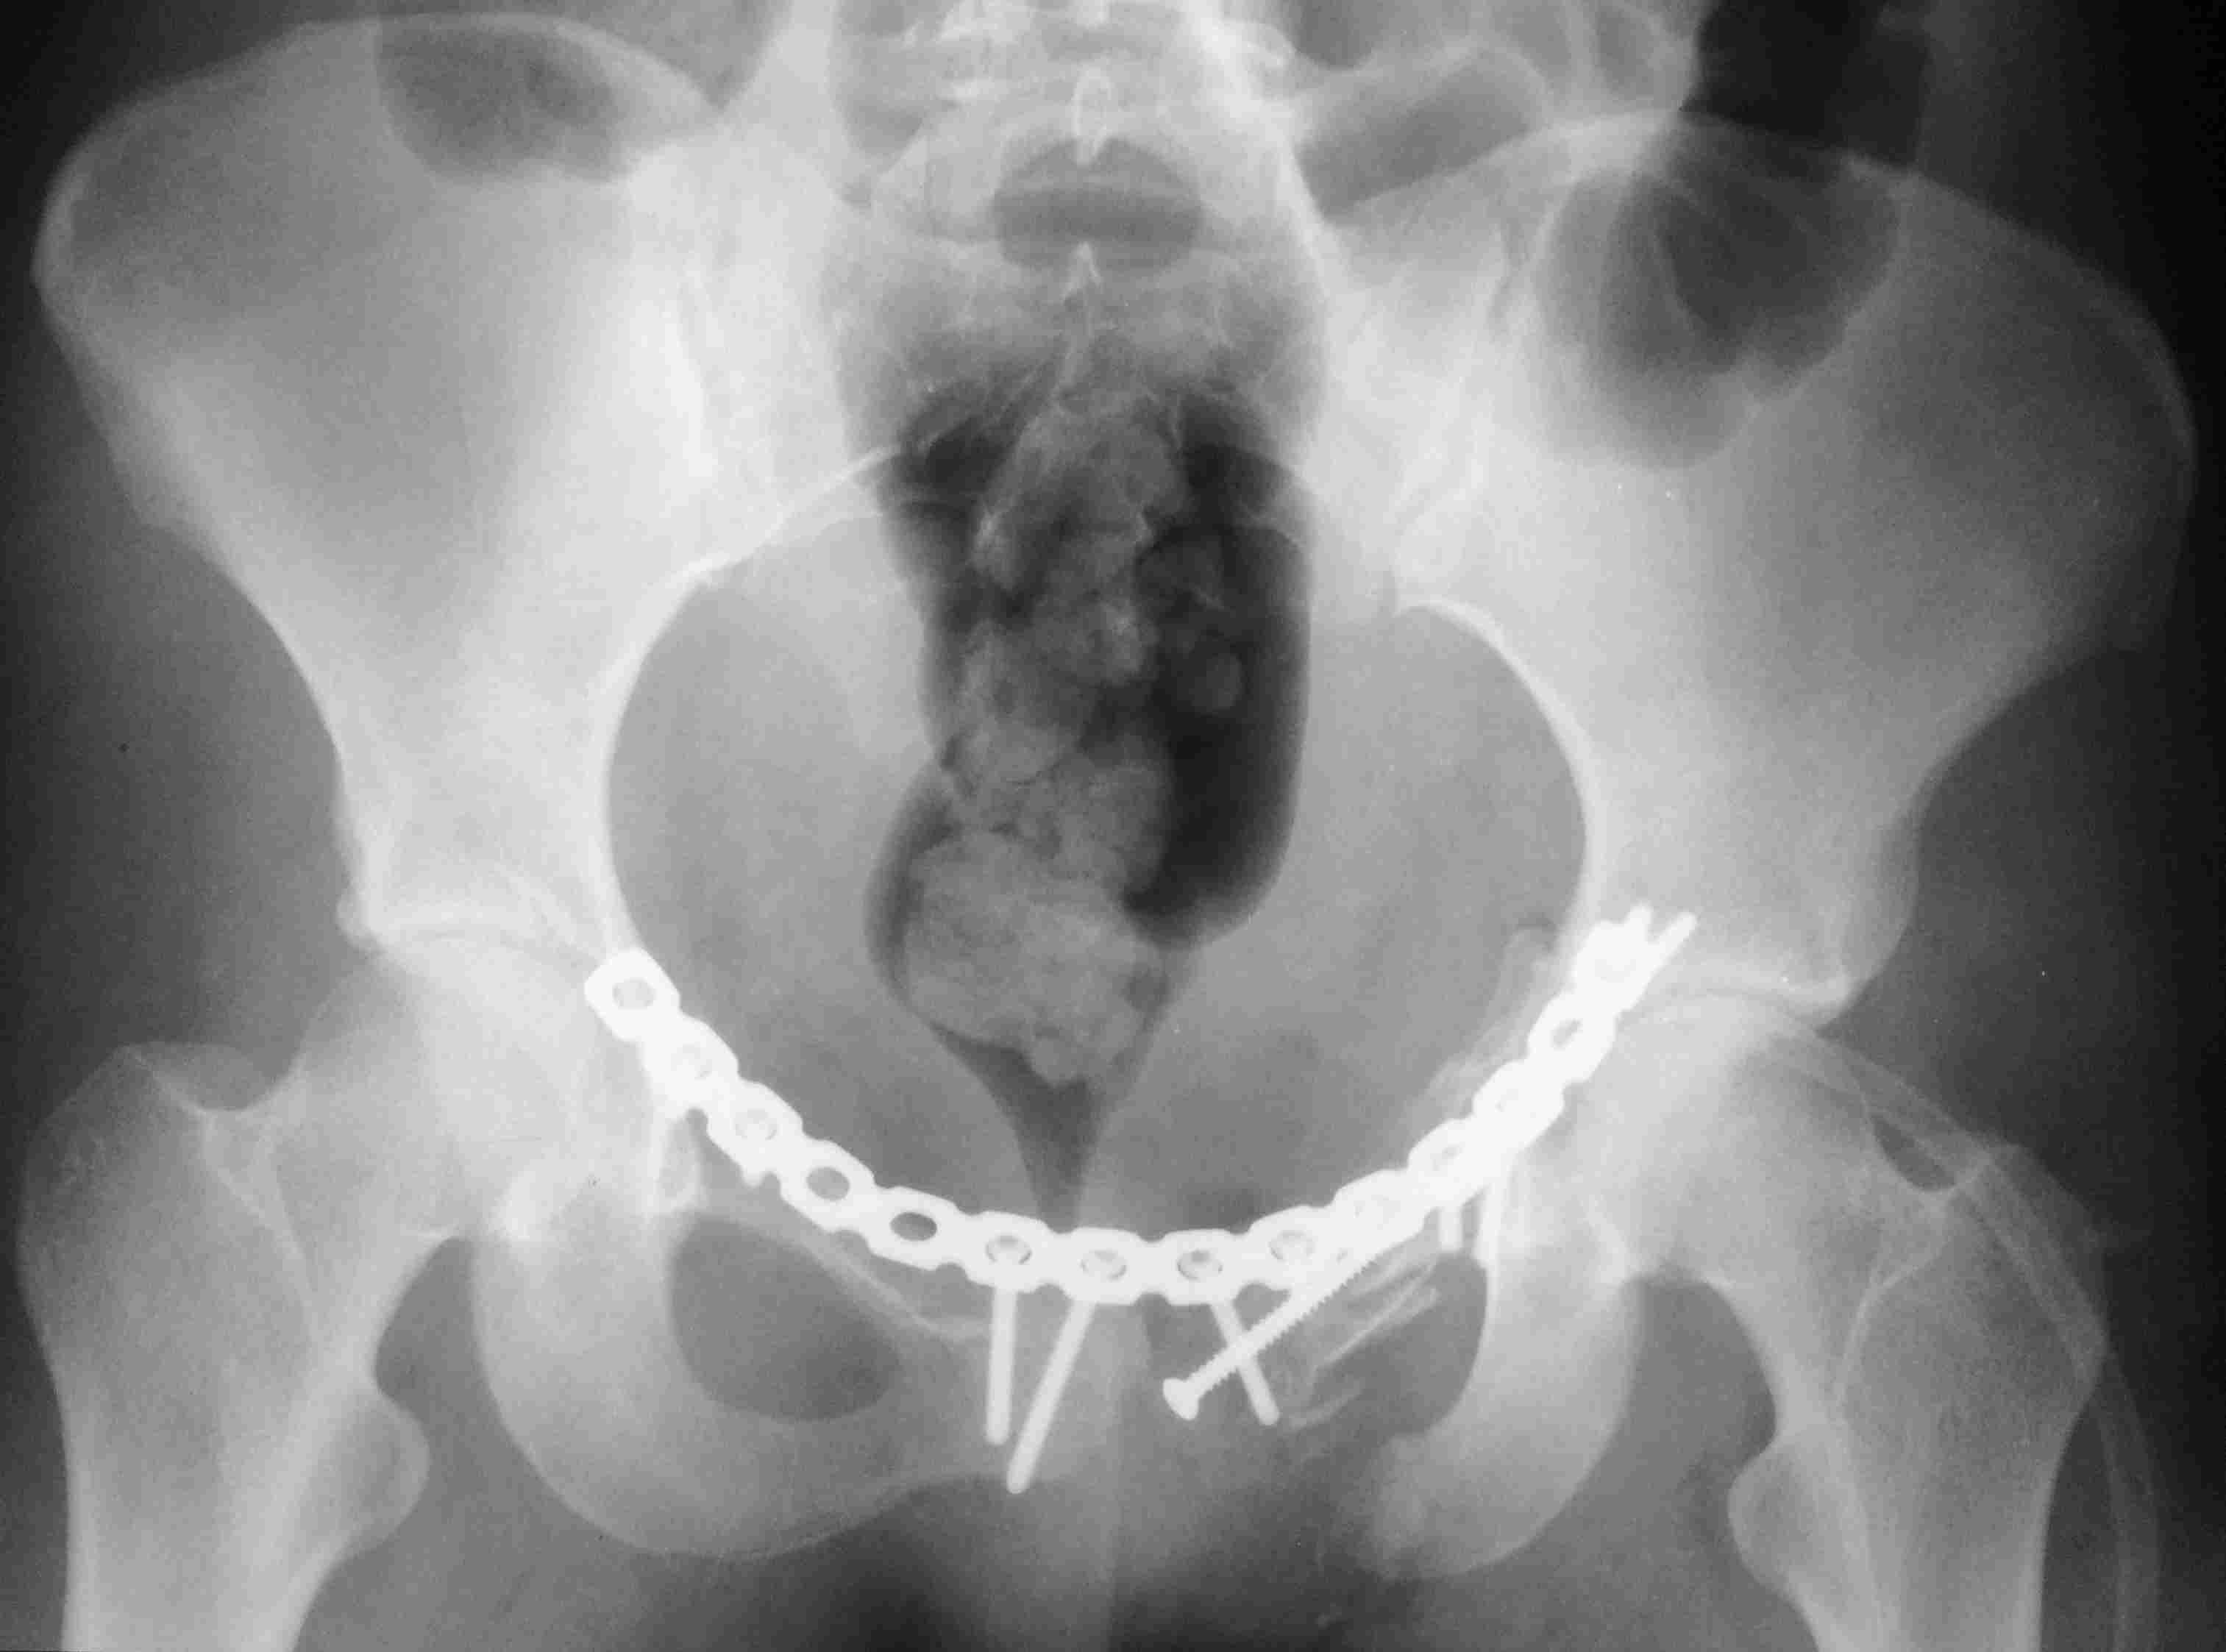

Женщина,21, социальна, без вредных превычек, сбита авто. Кожа не повреждена. Других повреждений нет. Гемодинамически стабильна. травме 2 сут. Планируем спереди открыто через Stoppa, далее сзади крестец и ость закрыто (крестец может через обе массы?). Интересует мнение по альтернативным вариантам и по предложенному (tricks and shots). Заранее благодарен.PS Только часть скринов с body scan, один с контрастированием пузыря.

Постоп. Верхняя ветвь возле шейки мочевого пузыря, нижняя так же где-то глубоко в мышцах, ротирована. Обе практически лишены кровоснабжения. лонное сочленение фактически свободно лежащее, справа почти целое, но ветви сломаны возле него. Слева часть лонного сочленения цела на 2/3. интраоперационно подвижность правой половины таза. Постоп все стабильно, но все же планирую дополнительно провести IS винт справа.

PS Нижнюю ветку нормально зафиксировать не получалось зафиксировать, уложил ее в виде чипсов туда, где она примерно была и вдоль верхней ветви слева